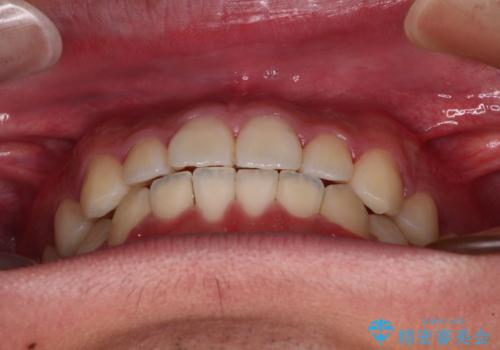

- 上下前歯の叢生を気にして来院された患者様です。

費用を抑え、期間もあまりかけずに治療をしたいとのことで、インビザライン・ライトを用いて矯正治療を行うこととしました。